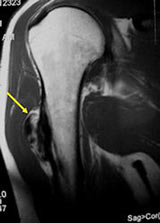

MRI/CT:

- Useful for determining medullary invasion

- Can help discern areas that may be high grade

- Most useful for evaluating the local extent of the tumor and relationship to neurovascular structures the circumference of the femur involved by the tumor (important for surgical planning)

- CT of chest is used for detecting pulmonary metastases

- Parosteal osteosarcomas that are present for prolonged periods of time may either have areas that become higher grade or dedifferentiate. Dedifferentiation refers to a portion of the tumor changing and becoming a high grade type of sarcoma. In addition, parosteal osteosarcomas that are present for a prolonged period of time can invade the bone (medullary canal) that it arose from. Tumors that have undergone dedifferentiation or invaded the underlying bone are more aggressive and have a higher risk of metastasizing (spreading). This is important to know for treatment purposes. Typically, low grade parosteal osteosarcomas are treated with surgery alone. Parosteal osteosarcomas with high grade areas may also be treated with chemotherapy in addition to surgery.

- There may be invasion of the medullary canal with long standing disease